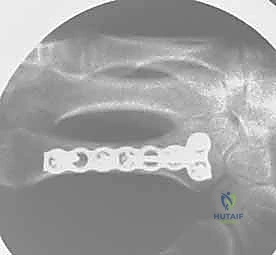

2. التثبيت الداخلي بالصفائح والبراغي المصغرة (Mini-Plates & Screws)

في حالات الكسور المتفتتة (Comminuted) أو الكسور الحلزونية الطويلة التي تميل للانزلاق، يلجأ الدكتور هطيف إلى التثبيت الداخلي المفتوح (ORIF). يتم استخدام صفائح معدنية دقيقة جداً (مصنوعة من التيتانيوم) تتناسب مع حجم عظام اليد.

* الميزة: تثبيت صلب وقوي جداً (Rigid Fixation)، مما يسمح للمريض ببدء العلاج الطبيعي وتحريك أصابعه في اليوم التالي للعملية، وهو أمر بالغ الأهمية لمنع تيبس الأوتار.

معرض الصور الشعاعية: تقييم النتائج الجراحية (Post-Op X-rays)

النجاح الحقيقي يُقاس بالاستعادة المثالية للشكل التشريحي للعظم. توضح هذه الصور الشعاعية بعد الجراحة الدقة المتناهية في إعادة محاذاة العظام وتثبيتها.

التثبيت المحكم يسمح بالشفاء العظمي الأولي (Primary Bone Healing) دون تكوين كتلة عظمية كبيرة (Callus) قد تعيق حركة الأوتار المنزلقة فوقها.